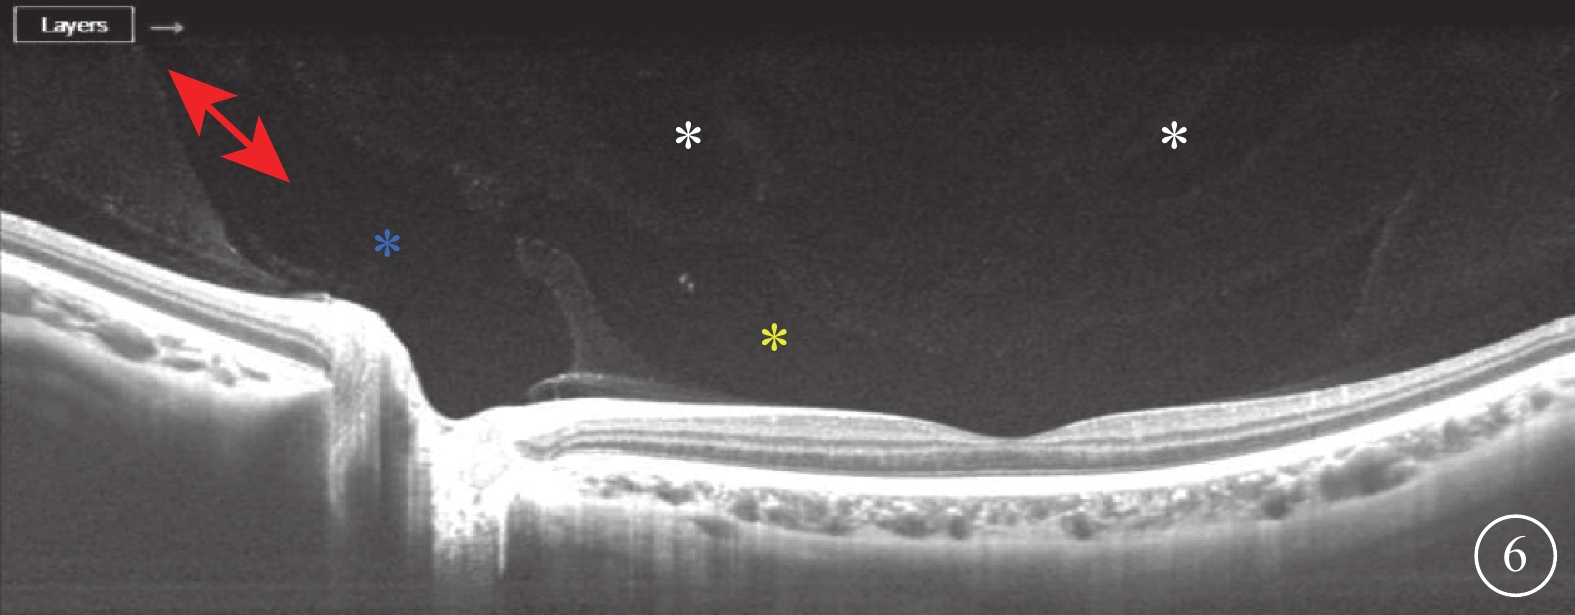

SD-OCT檢查,所有受檢眼常規檢查均未觀察到PPVP。后極部玻璃體掃描模式所采集的圖像可見PPVP結構清晰,表現為黃斑區前弱反射船形腔隙,前界為玻璃體膠原,后界為玻璃體皮質(圖2)。所有受檢眼PPVP鼻側存在一弱反射的無凝膠區域(Martegiani區),兩者之間有一隔膜將其分開。其中,單線掃描可見PPVP與Martegiani區之間存在連接通道(圖2)68只眼(66.0%);多線掃描可見所有受檢眼PPVP與Martegiani區存在連接通道,通道在某些層面出現(圖3)。PPVP前可見一個或多個黃斑上囊(圖2)16只眼(15.5%),其中黃斑上囊與PPVP之間相互連通(圖4)5只眼。PPVP伴玻璃體后脫離(PVD)(圖5)9只眼。采用FDI掃描模式進行檢查的21只眼,視網膜、脈絡膜成像清晰度較好,但玻璃體成像清晰度較差(圖4)。60只眼的PPVP平均最大水平距離為(6 895.7± 872.8)μm,平均垂直距離為(524.1±173.9)μm。

圖5

受檢眼SD-OCT像。PPVP(黃星)伴不完全性PVD(白箭)

圖5

受檢眼SD-OCT像。PPVP(黃星)伴不完全性PVD(白箭)

SD-OCT檢查,所有受檢眼常規檢查均未觀察到PPVP。后極部玻璃體掃描模式所采集的圖像可見PPVP結構清晰,表現為黃斑區前弱反射船形腔隙,前界為玻璃體膠原,后界為玻璃體皮質(圖2)。所有受檢眼PPVP鼻側存在一弱反射的無凝膠區域(Martegiani區),兩者之間有一隔膜將其分開。其中,單線掃描可見PPVP與Martegiani區之間存在連接通道(圖2)68只眼(66.0%);多線掃描可見所有受檢眼PPVP與Martegiani區存在連接通道,通道在某些層面出現(圖3)。PPVP前可見一個或多個黃斑上囊(圖2)16只眼(15.5%),其中黃斑上囊與PPVP之間相互連通(圖4)5只眼。PPVP伴玻璃體后脫離(PVD)(圖5)9只眼。采用FDI掃描模式進行檢查的21只眼,視網膜、脈絡膜成像清晰度較好,但玻璃體成像清晰度較差(圖4)。60只眼的PPVP平均最大水平距離為(6 895.7± 872.8)μm,平均垂直距離為(524.1±173.9)μm。

圖5

受檢眼SD-OCT像。PPVP(黃星)伴不完全性PVD(白箭)

圖5

受檢眼SD-OCT像。PPVP(黃星)伴不完全性PVD(白箭)